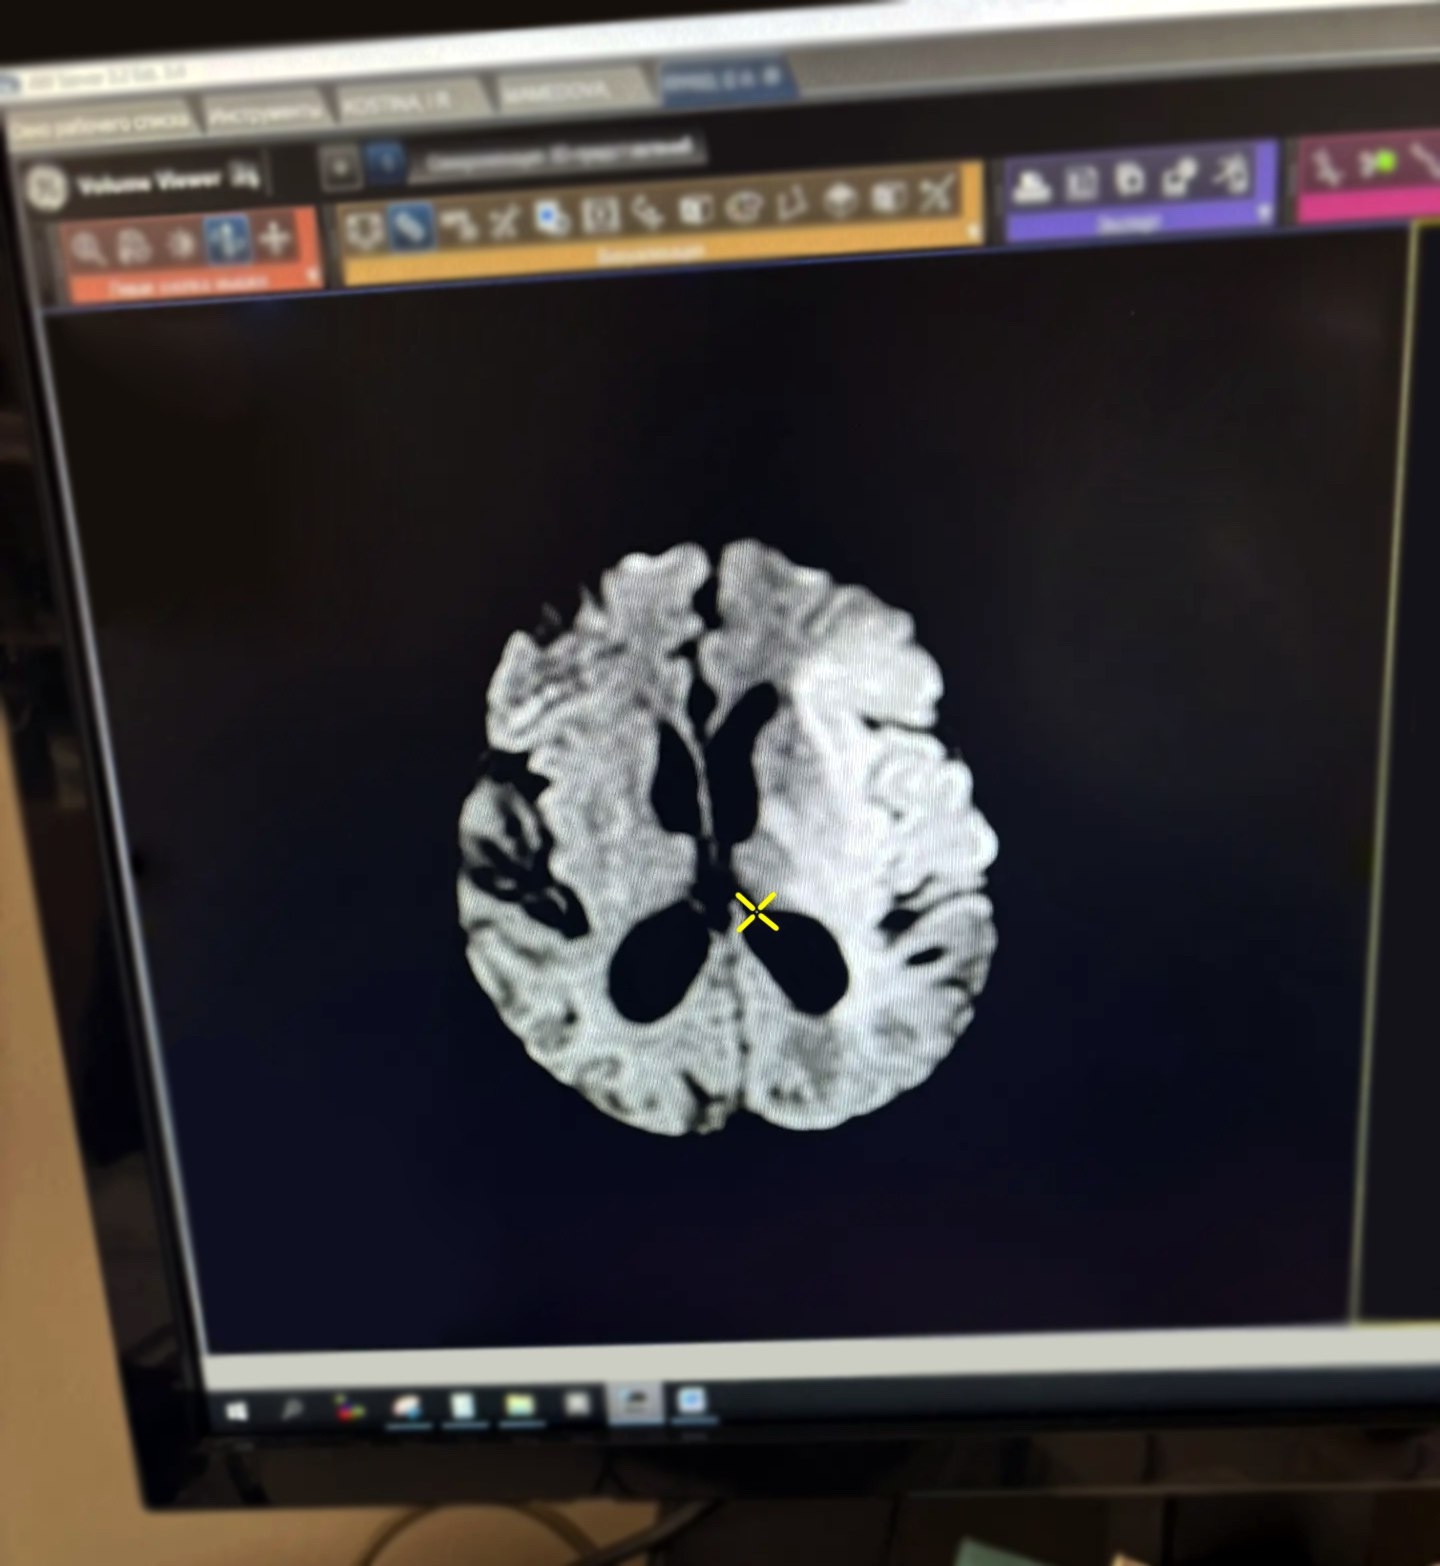

Пациенту провели тромболитическую терапию. После восьми дней наблюдения в стационаре его выписали домой на девятый день для дальнейшего наблюдения по месту жительства.